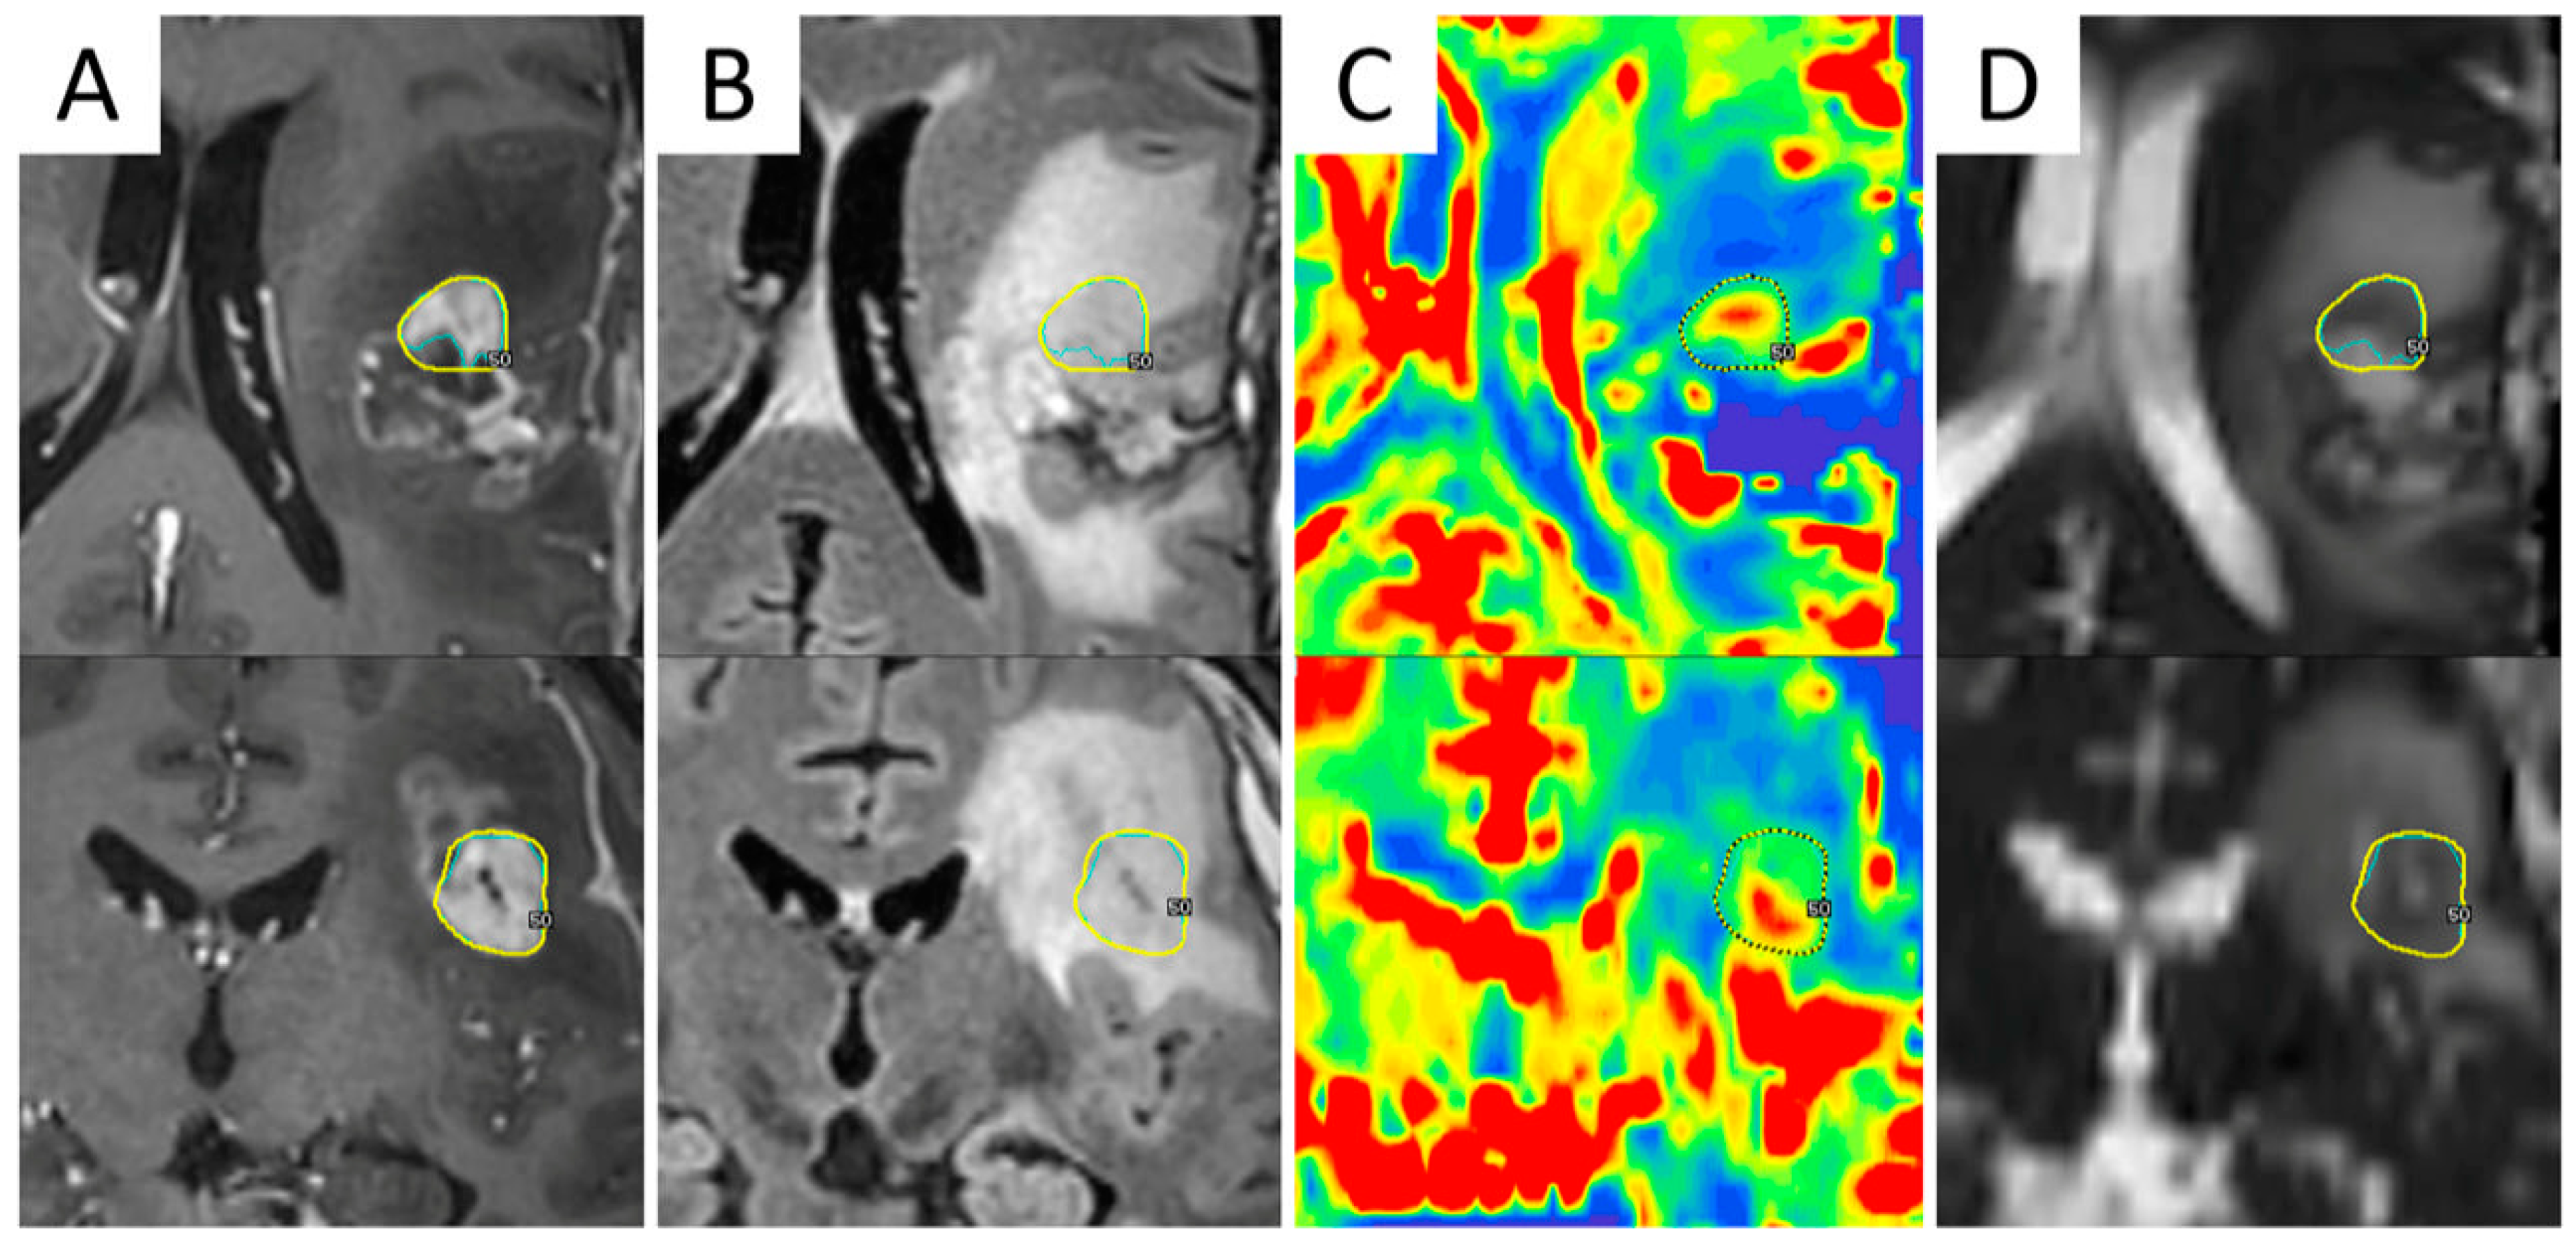

Figure 2.

Integration of advanced MRI sequences in a Gamma Knife radiosurgical planning of a 44-year-old male patient with recurrent WHO grade III astrocytoma after multimodal first-line therapy and recent redo surgery with maximum safe resection. Axial (upper row) and coronal (bottom row) views of contrast-enhanced T1-weighted (A) and fluid-attenuated inversion recovery (FLAIR) (B) MRI images, co-registered with relative cerebral blood volume (rCBV) map (C) and apparent diffusion coefficient (ADC) map (D), demonstrating how different sequences identify different volumes of disease. The final target was determined as the nodule showing hyper-intensity in post-contrast T1-weighted sequences, hypo-intensity in ADC maps, and elevated perfusion values on the rCBV map.